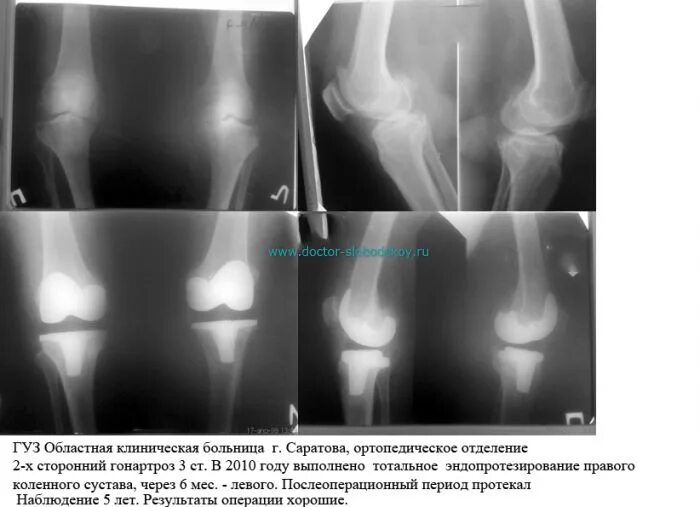

Нестабильность коленного сустава симптомы